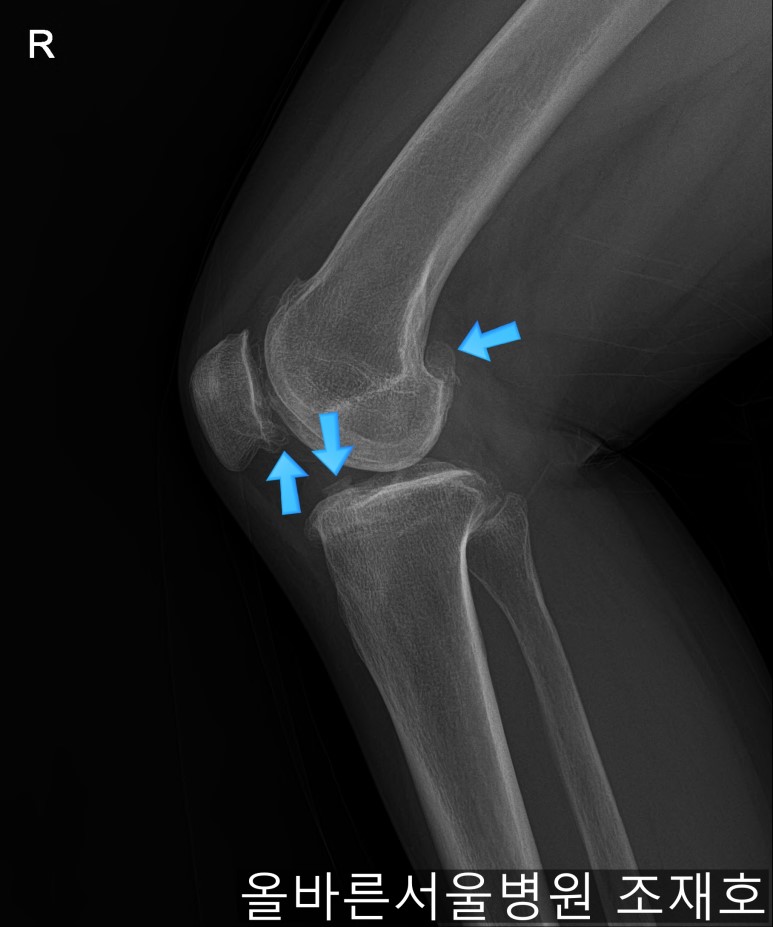

某患者,女,54岁,大面积软骨损伤,伴随内翻畸形,实施非切开CARTSTIEM手术及胫骨近端外翻截骨术,2、3年前右侧膝盖开始疼痛,在其他医院做了两次关节镜手术后疼痛加剧,膝关节变形严重遂到本院接受治疗。

仅通过放射线片子观察到:右膝由于炎症严重,内侧胫骨及股骨已接触在一起,向内测严重变形。

如果通过X光片也观察到相同的病症,可以判断内侧关节的软骨大部分都损伤了。

通过观察侧位片子可看到:由于关节炎已经长出骨刺。髌骨关节有炎症。